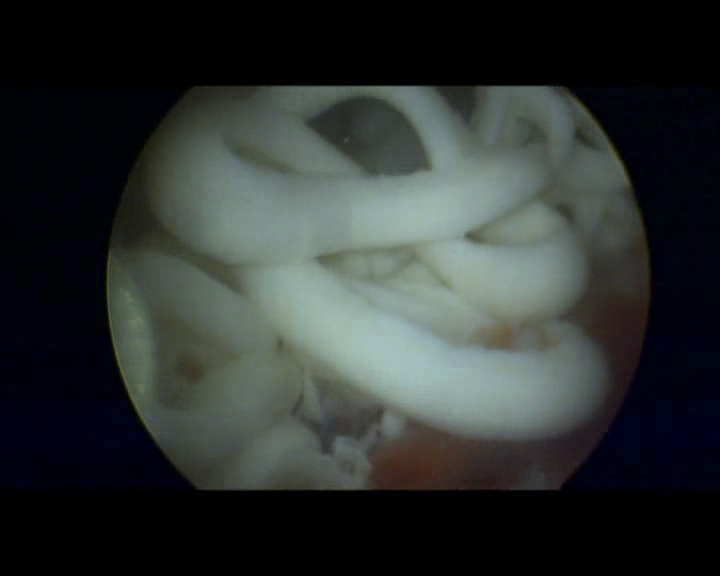

陆阿姨于今年7月来到广西中医药大学附属瑞康医院关节与运动医学科门诊就医,经过医生的详细检查,拍X光片后发现右肩部肩袖区有明显的钙化灶,才知道自己得的是“右肩关节钙化性肌腱炎”,陆阿姨在震惊之余也看到了希望,关节与运动医学科李书振主任认真细致地跟她分析了病情及解决方案,由于长时间的求医路和肩部疼痛难忍影响到了正常生活,陆阿姨马上住进了瑞康医院关节与运动医学科,并接受了“经肩关节镜微创手术”治疗,手术中从陆阿姨的肩膀里竟然挤出了许多白色的牙膏样物质,这就是已经钙化的肌腱组织。手术当晚陆阿姨的右肩疼痛明显减轻,3年来终于可以睡个好觉了,现在陆阿姨的肩部病痛已经彻底解决,已经恢复了正常生活。

术中挤出牙膏样物质